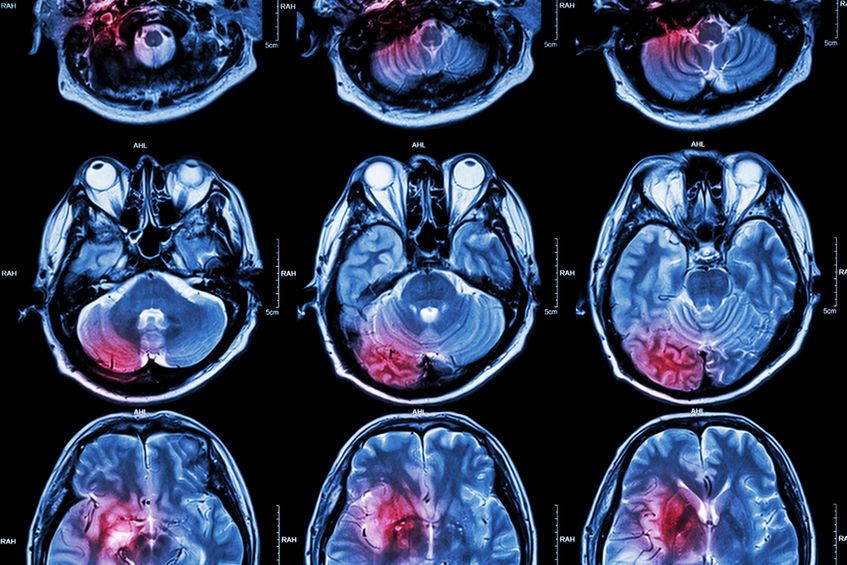

Agnozja może być manifestacją poważnego uszkodzenia mózgu

Agnozja może być manifestacją poważnego uszkodzenia mózgu © 123RF

W dalszej kolejności może okazać się konieczne przeprowadzenie badania neurologicznego, czy też diagnostyki obrazowej, takiej jak tomografia komputerowa, czy też rezonans magnetyczny, których celem będzie ustalenie choroby podstawowej, która jest odpowiedzialna za wystąpienie objawów agnozji.